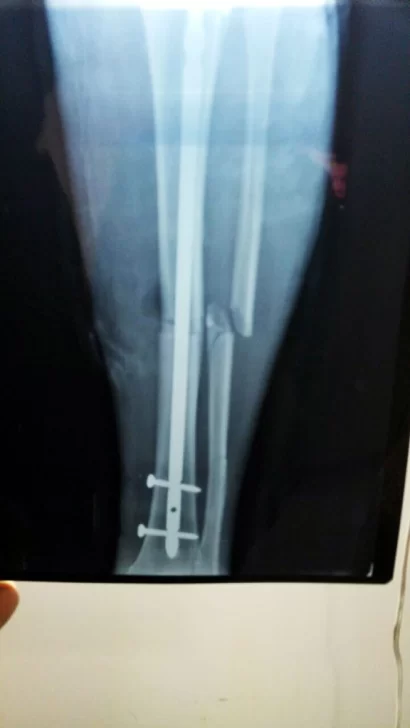

Fuentes consultadas por La Opinión Austral indicaron que la denuncia fue por mala praxis, negligencia y alteración de historia clínica. En resumen, acusan a la facultativa de no tomar los recaudos necesarios para el tratamiento de su paciente. Cecilia es la hija de Sergio Girardi. Su padre se accidentó en el mes de enero a bordo de una motocicleta en la ruta nacional 3. Este incidente hizo que debiera colocársele una prótesis en la pierna donde sufrió fracturas.

La denunciante arribó desde Córdoba para ayudar a su padre y madre ante este inconveniente que vienen arrastrando hace ya tiempo. En la denuncia se apunta que post operación el hombre sufrió hemorragias y que la atención en el Hospital Regional por parte de la doctora Andrea Balarino nunca fue la necesaria.

Cuando su situación se “regularizó”, fue dado de alta y comendado a realizar fisioterapia, pero continuó con problemas que la profesional médica “desestimaba”, cuestionaron. A Girardi se le generó una úlcera en la pierna y en el mes de marzo tuvo un shock séptico por la infección.

Girardi fue derivado a Buenos Aires, en donde deberá ser nuevamente intervenido quirúrgicamente.